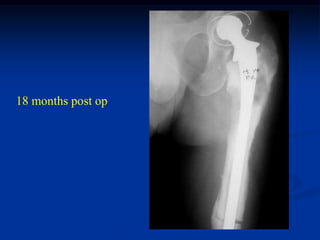

5 months post op with

radiolucent cement

18 months post op